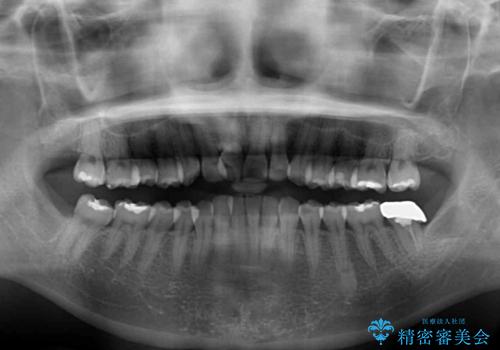

- 上下前歯のデコボコと奥歯の銀歯を気にして来院された患者様です。

口元をインビザラインにより歯列を整え、その後に失活している奥歯をオールセラミッククラウンにて補綴治療することとしました。